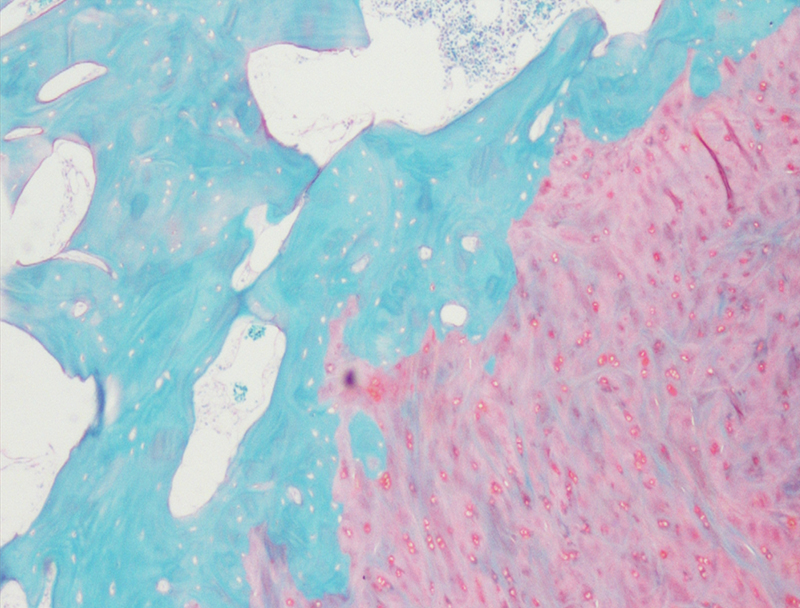

番红-固绿染色

番红-固绿染色(软骨)在涉及关节软骨及软骨下骨的形态学研究中,常需联合使用多种染料以显示其组织学结构。其中,起源于上世纪60年代的番红O(safranin O)-固绿(fast green)染色因可以直观反映关节软骨、软骨下骨和骨组织的结构而备受青睐。软骨呈红色,成骨呈绿色。

番红-固绿(软骨)染色法的染色原理在于嗜碱性的软骨和碱性染料番红O结合呈现红色,嗜酸性的骨和酸性染料固绿结合而成绿色或者蓝色,与呈现红色的软骨对比鲜明,从而将软骨组织和骨组织区分开。番红O是一种结合多阴离子的阳离子染料,其显示软骨组织是基于阳离子染料与多糖中阴离子基团(硫酸软骨素或硫酸角质素)结合。番红O着色与阴离子的浓度近似成正比关系,间接反映基质中蛋白多糖的含量和分布。当软骨收到损伤时,软骨中的糖蛋白会释放出来,使基质成分分布不均匀,从而导致番红O淡染或不着色。通过图像分析软件可以对番红O染色的软骨基质进行定量分析。固绿与胶原纤维结合,不宜褪色。

<<>番红固绿-骨>